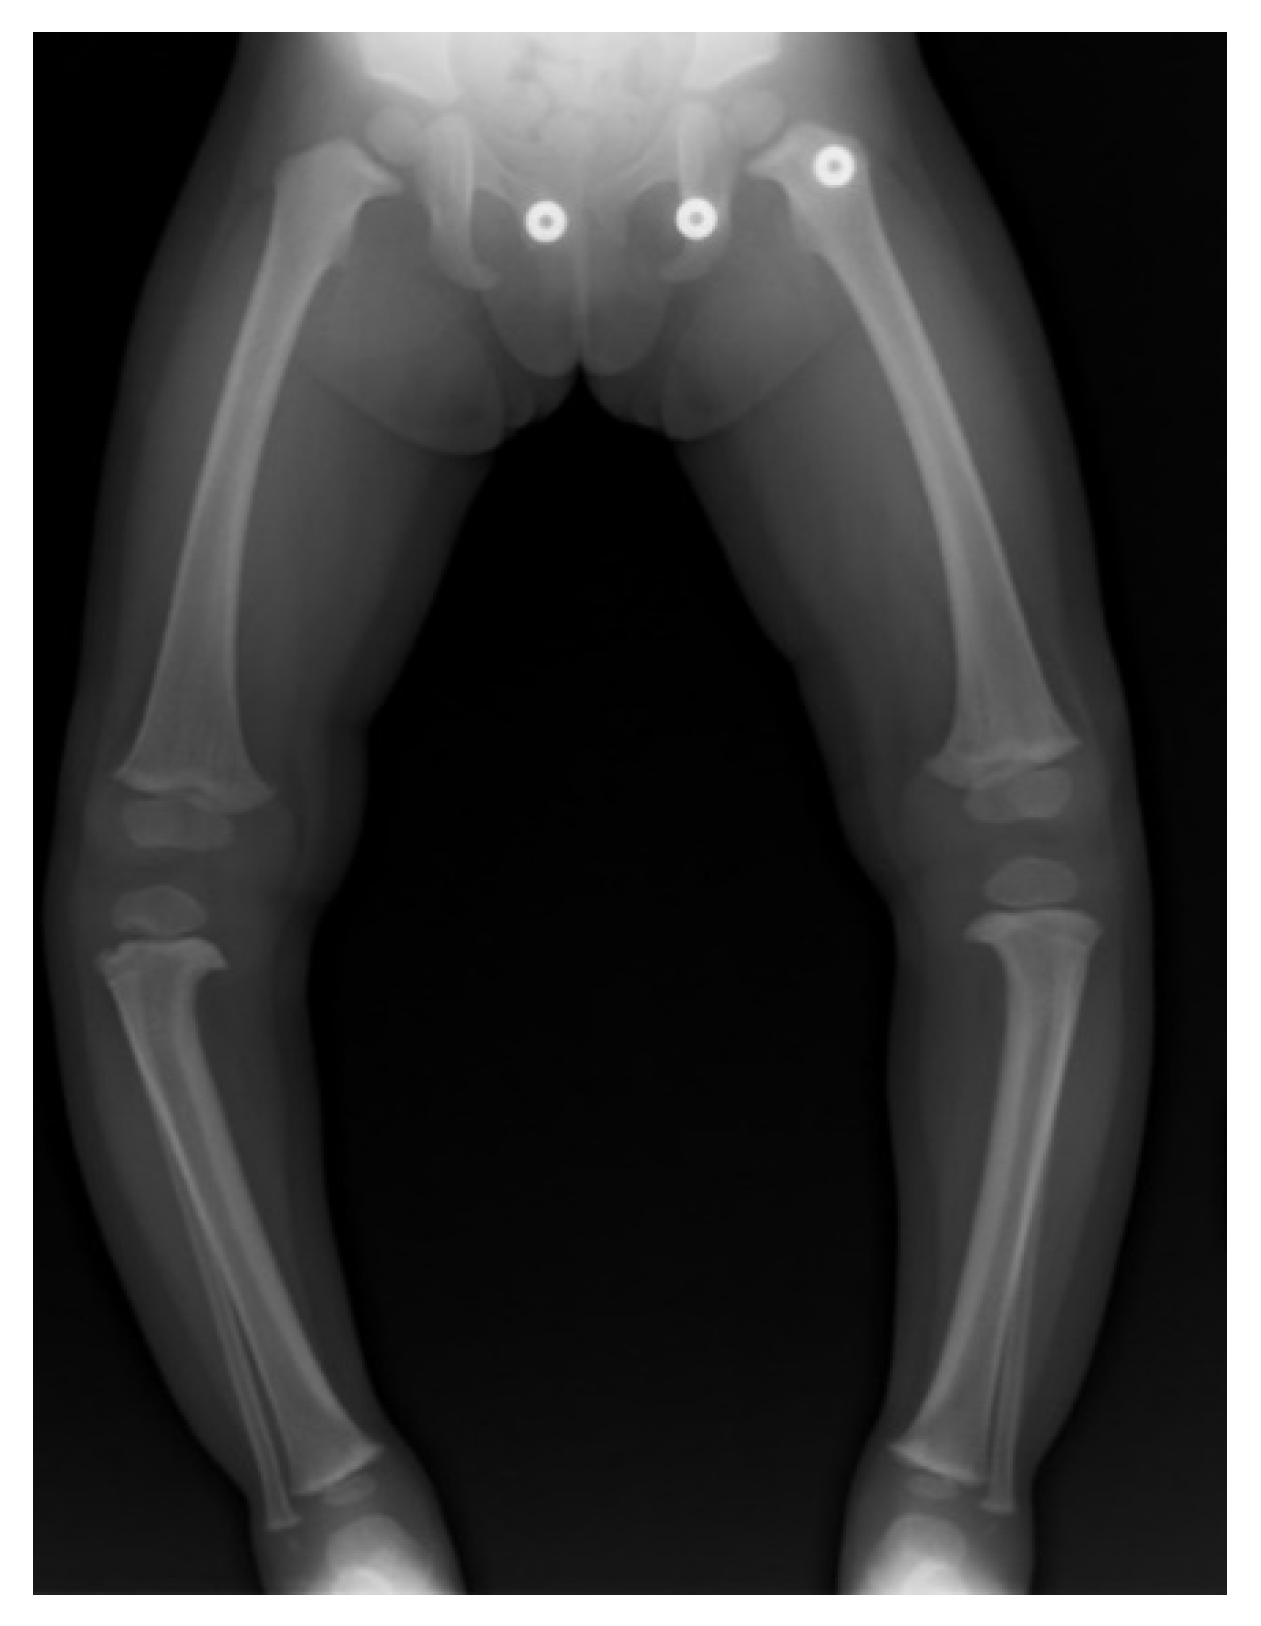

17. Gradual Correction with External Fixation

18. Late-Onset Tibia Vara (LOTV)